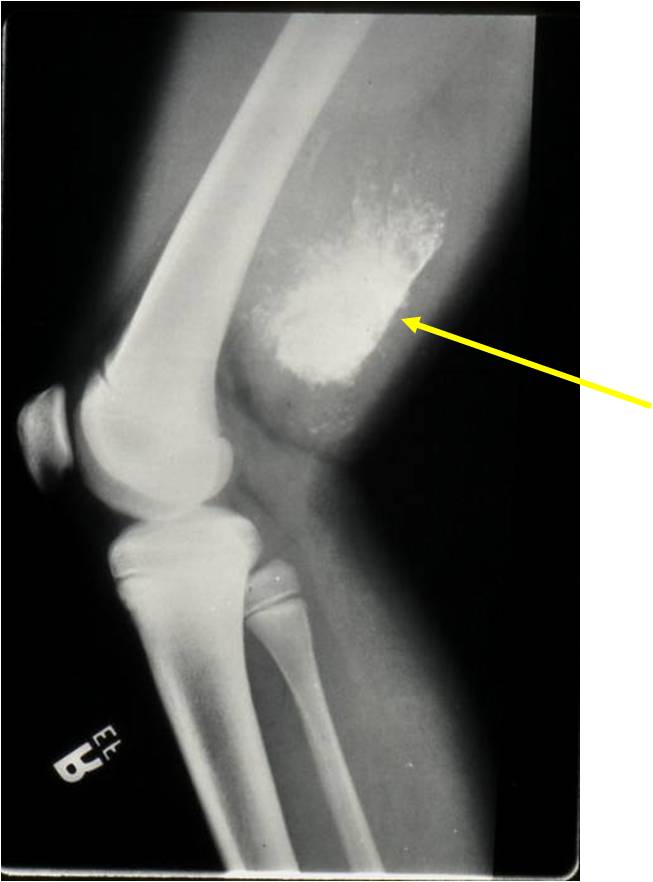

- Aggressive motheaten to permeative lesion

- Indistinct border in most cases

- Osseous destruction with a soft tissue component

- Chondroid matrix calcification may be present (60-70% of cases)

- Soft tissue mass

(Right Arrow) Cartilaginous Component